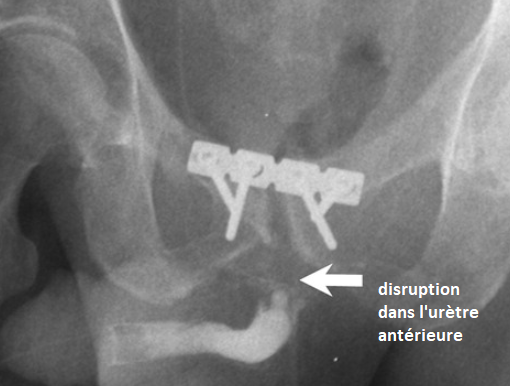

Classification de Goldman

Goldman I

Goldman II

Godlman III

Goldman IV

Goldman IVa

urètral urethral urètrhal uretral urètre urèthre trauma traumatisme choc lésion fracture rutpure

urètral urethral urètrhal uretral urètre urèthre trauma traumatisme choc lésion fracture rutpure